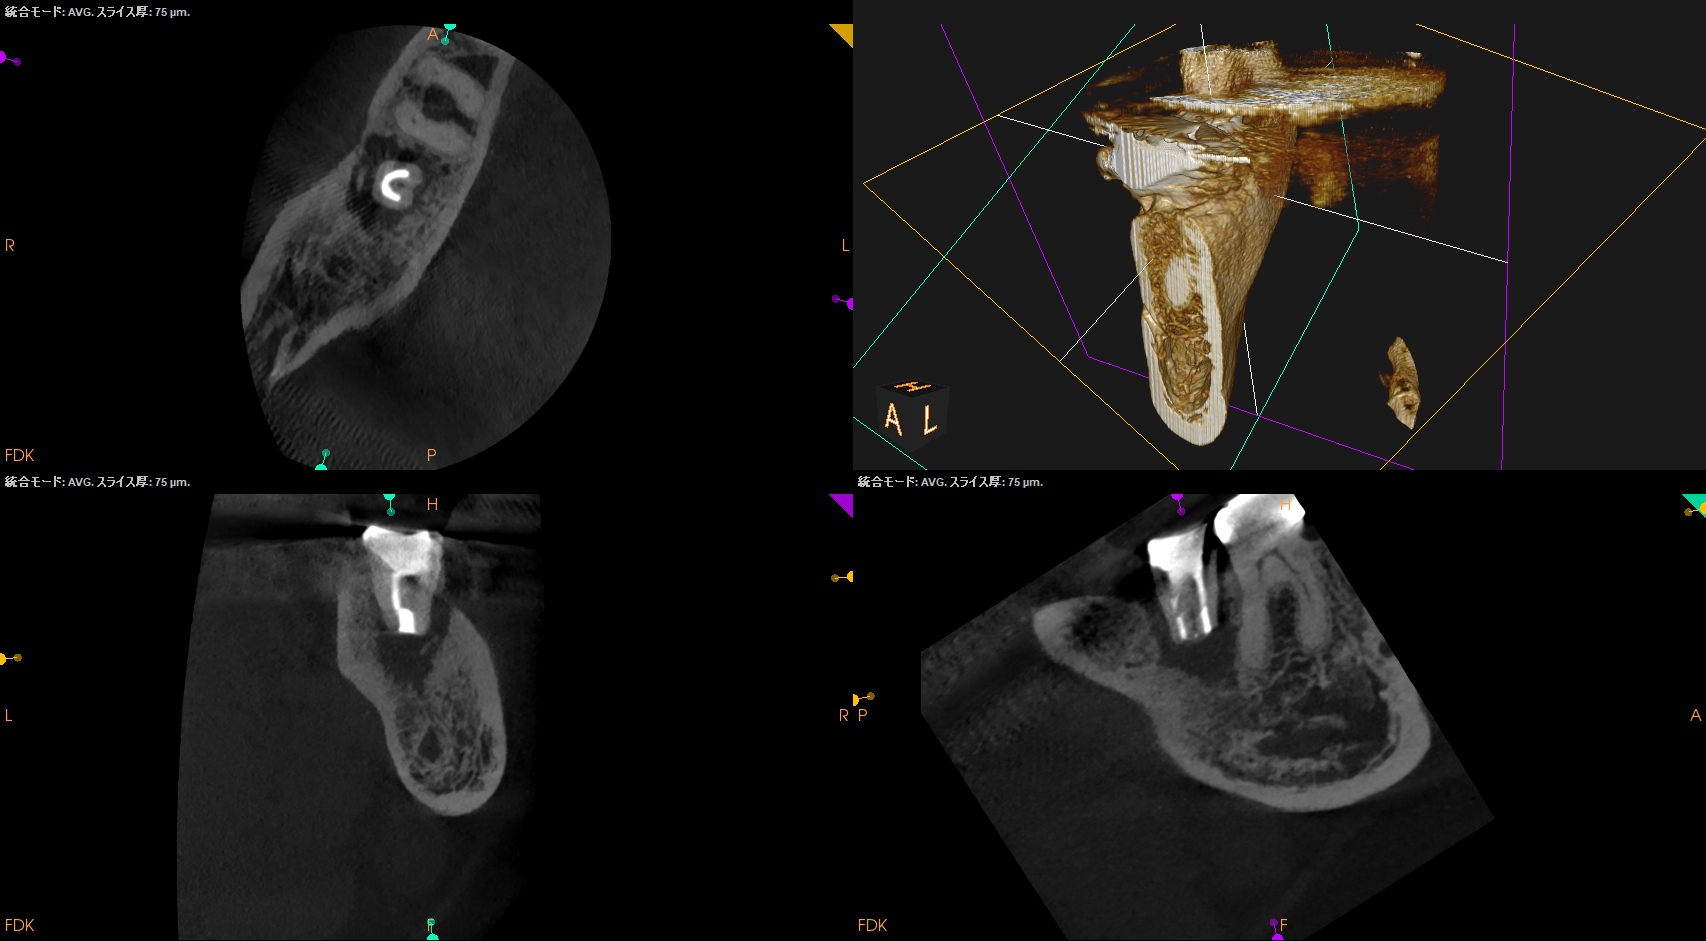

CBCT(2025.5.19)

ML

MB

D

確かに…

折れていると言われかねない状況だ。